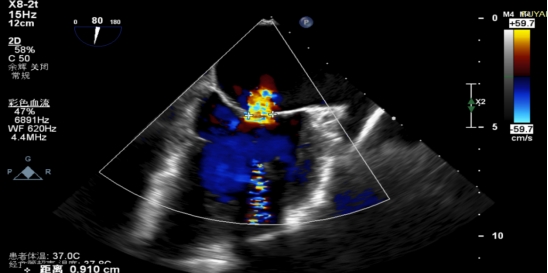

手术当日,在全身麻醉及TEE全程导航下,陈玺全副主任团队凭借丰富的临床经验与精湛操作技巧,顺利完成房间隔穿刺、瓣叶精准定位等关键步骤。针对患者二尖瓣A2/P2 区域反流靶点,团队精准夹合瓣叶,经X-plane技术与三维超声反复确认夹持质量后,成功释放一枚MitraClip XTR夹子。术后即时评估显示,患者二尖瓣反流由术前3 +重度降至轻度,平均跨瓣压仅3mmHg,手术达到预期效果,全程无并发症发生。

术后PV前向改善

术后第二天,患者顺利返回普通病房,并可自主下床活动,进食、睡眠等生活状态逐步恢复正常。术后超声显示残余轻度反流,肺静脉血流恢复正常,患者症状较前明显改善,活动耐量提升,生活质量显著提高。术后1周,患者各项生命体征平稳,顺利康复出院。“没想到不用开胸就解决了这个大毛病,还能恢复这么快、这么好!”出院当天,患者及家属对手术效果和就医体验给予高度评价,并衷心感谢医护人员的专业诊疗和无微不至的关怀照护。